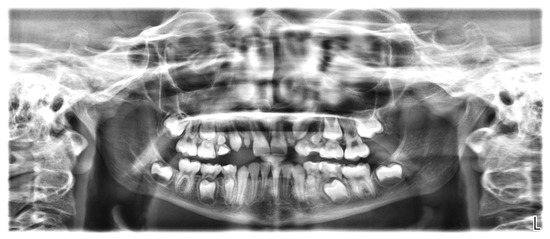

2.4. Radiological Examination